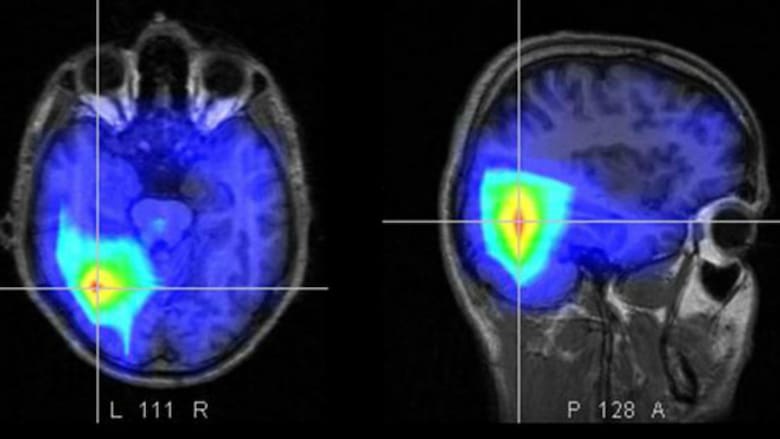

Un reciente informe de The Lancet Regional Health enciende las alarmas: el accidente cerebrovascular (ACV), tradicionalmente asociado a mayores de 60 años, está irrumpiendo con fuerza entre los adultos jóvenes de la región. “En la Argentina, aproximadamente el 15% de todos los ACV ocurre en personas de entre 18 y 55 años”, señala Matías Baldoncini, integrante del Servicio de Neurocirugía del Hospital Petrona V. de Cordero de San Fernando.

Entre 1990 y 2015, las tasas de ACV ajustadas por edad mostraron un descenso alentador. Sin embargo, el estudio advierte que desde entonces la incidencia de accidentes cerebrovasculares en adultos jóvenes ha registrado un crecimiento sostenido. El estudio, que abarcó datos de 38 países y territorios entre 1990 y 2021, muestra aumentos sostenidos en incidencia, mortalidad y carga de años de vida ajustados por discapacidad (DALY).